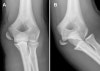

X-ray : 내상과 골절(medial epicondyle fracture), unstable